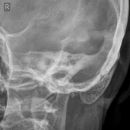

Schädel lateral

Vollständige Darstellung des gesamten Schädels, weitgehend deckend der Konturen, vordere und hintere Schädelgrube, Orbita, Kieferhöhlen und Jochbein. Zudem deckungsgleich von kleiner Keilbeinflügel und äußerer Gehörgang. Strichförmige Abbildung der Sella turcica.